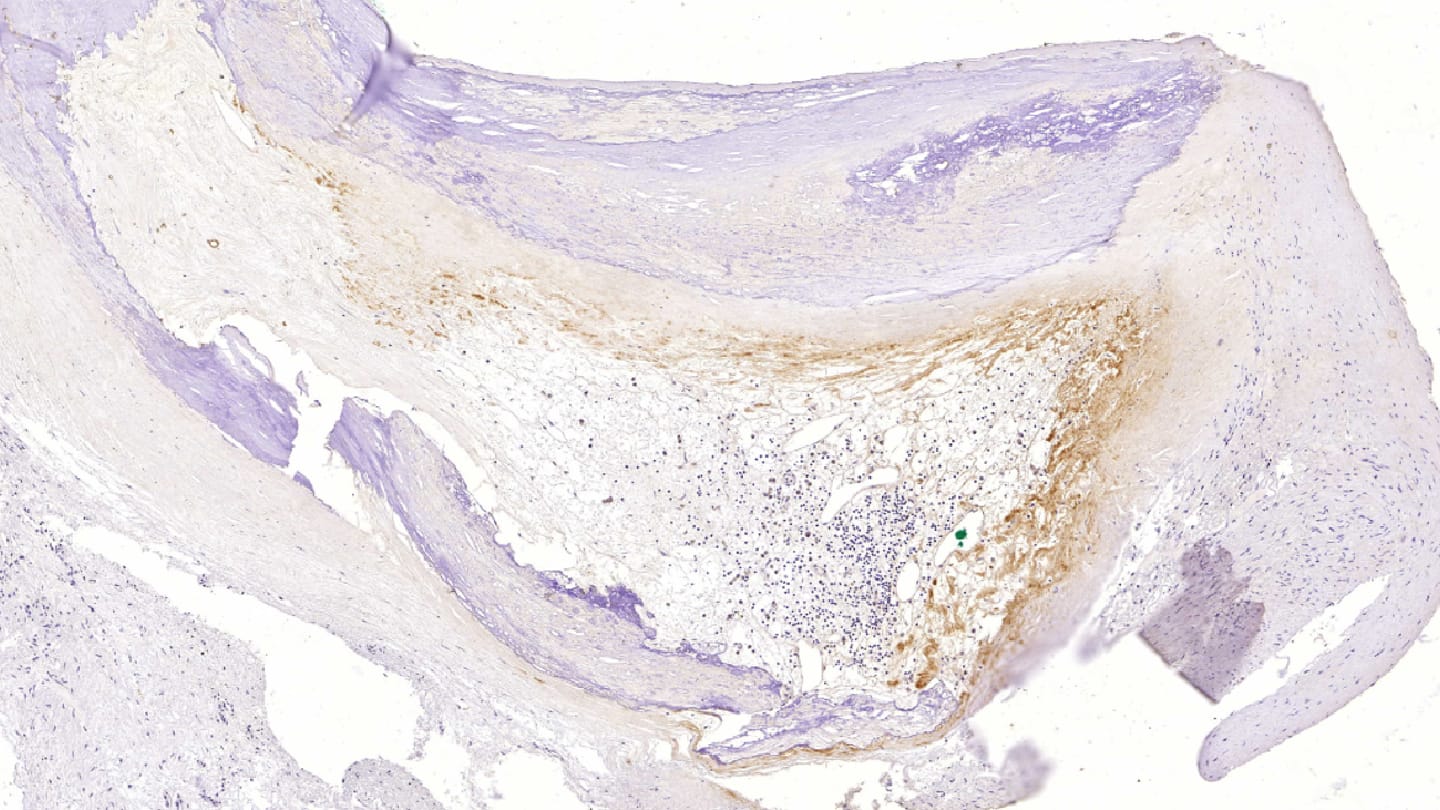

The main challenge, of course, was that our initial material consisted of postmortem coronary samples, raising the possibility that the detected bacteria were contaminants. However, contaminant organisms do not trigger immune recognition or an inflammatory response – both of which we were able to demonstrate in these samples. In addition, we analyzed carotid, aortic, and femoral artery specimens from surgical patients and replicated both the bacterial DNA findings and the immunohistochemical staining results. This consistency across living and postmortem material further argues against postmortem contamination.

We also encountered significant technical difficulties when preparing the heavily calcified arterial samples for histology. Sectioning them on a microtome and ensuring the sections adhered to slides proved challenging. The samples required up to two weeks of EDTA decalcification, and EDTA had to be applied directly to the block immediately before cutting to obtain sections with as little fragmentation as possible. It also took time to identify microscope slides capable of holding these sections effectively. Extracting DNA from calcified tissue was similarly demanding and required extensive optimization.